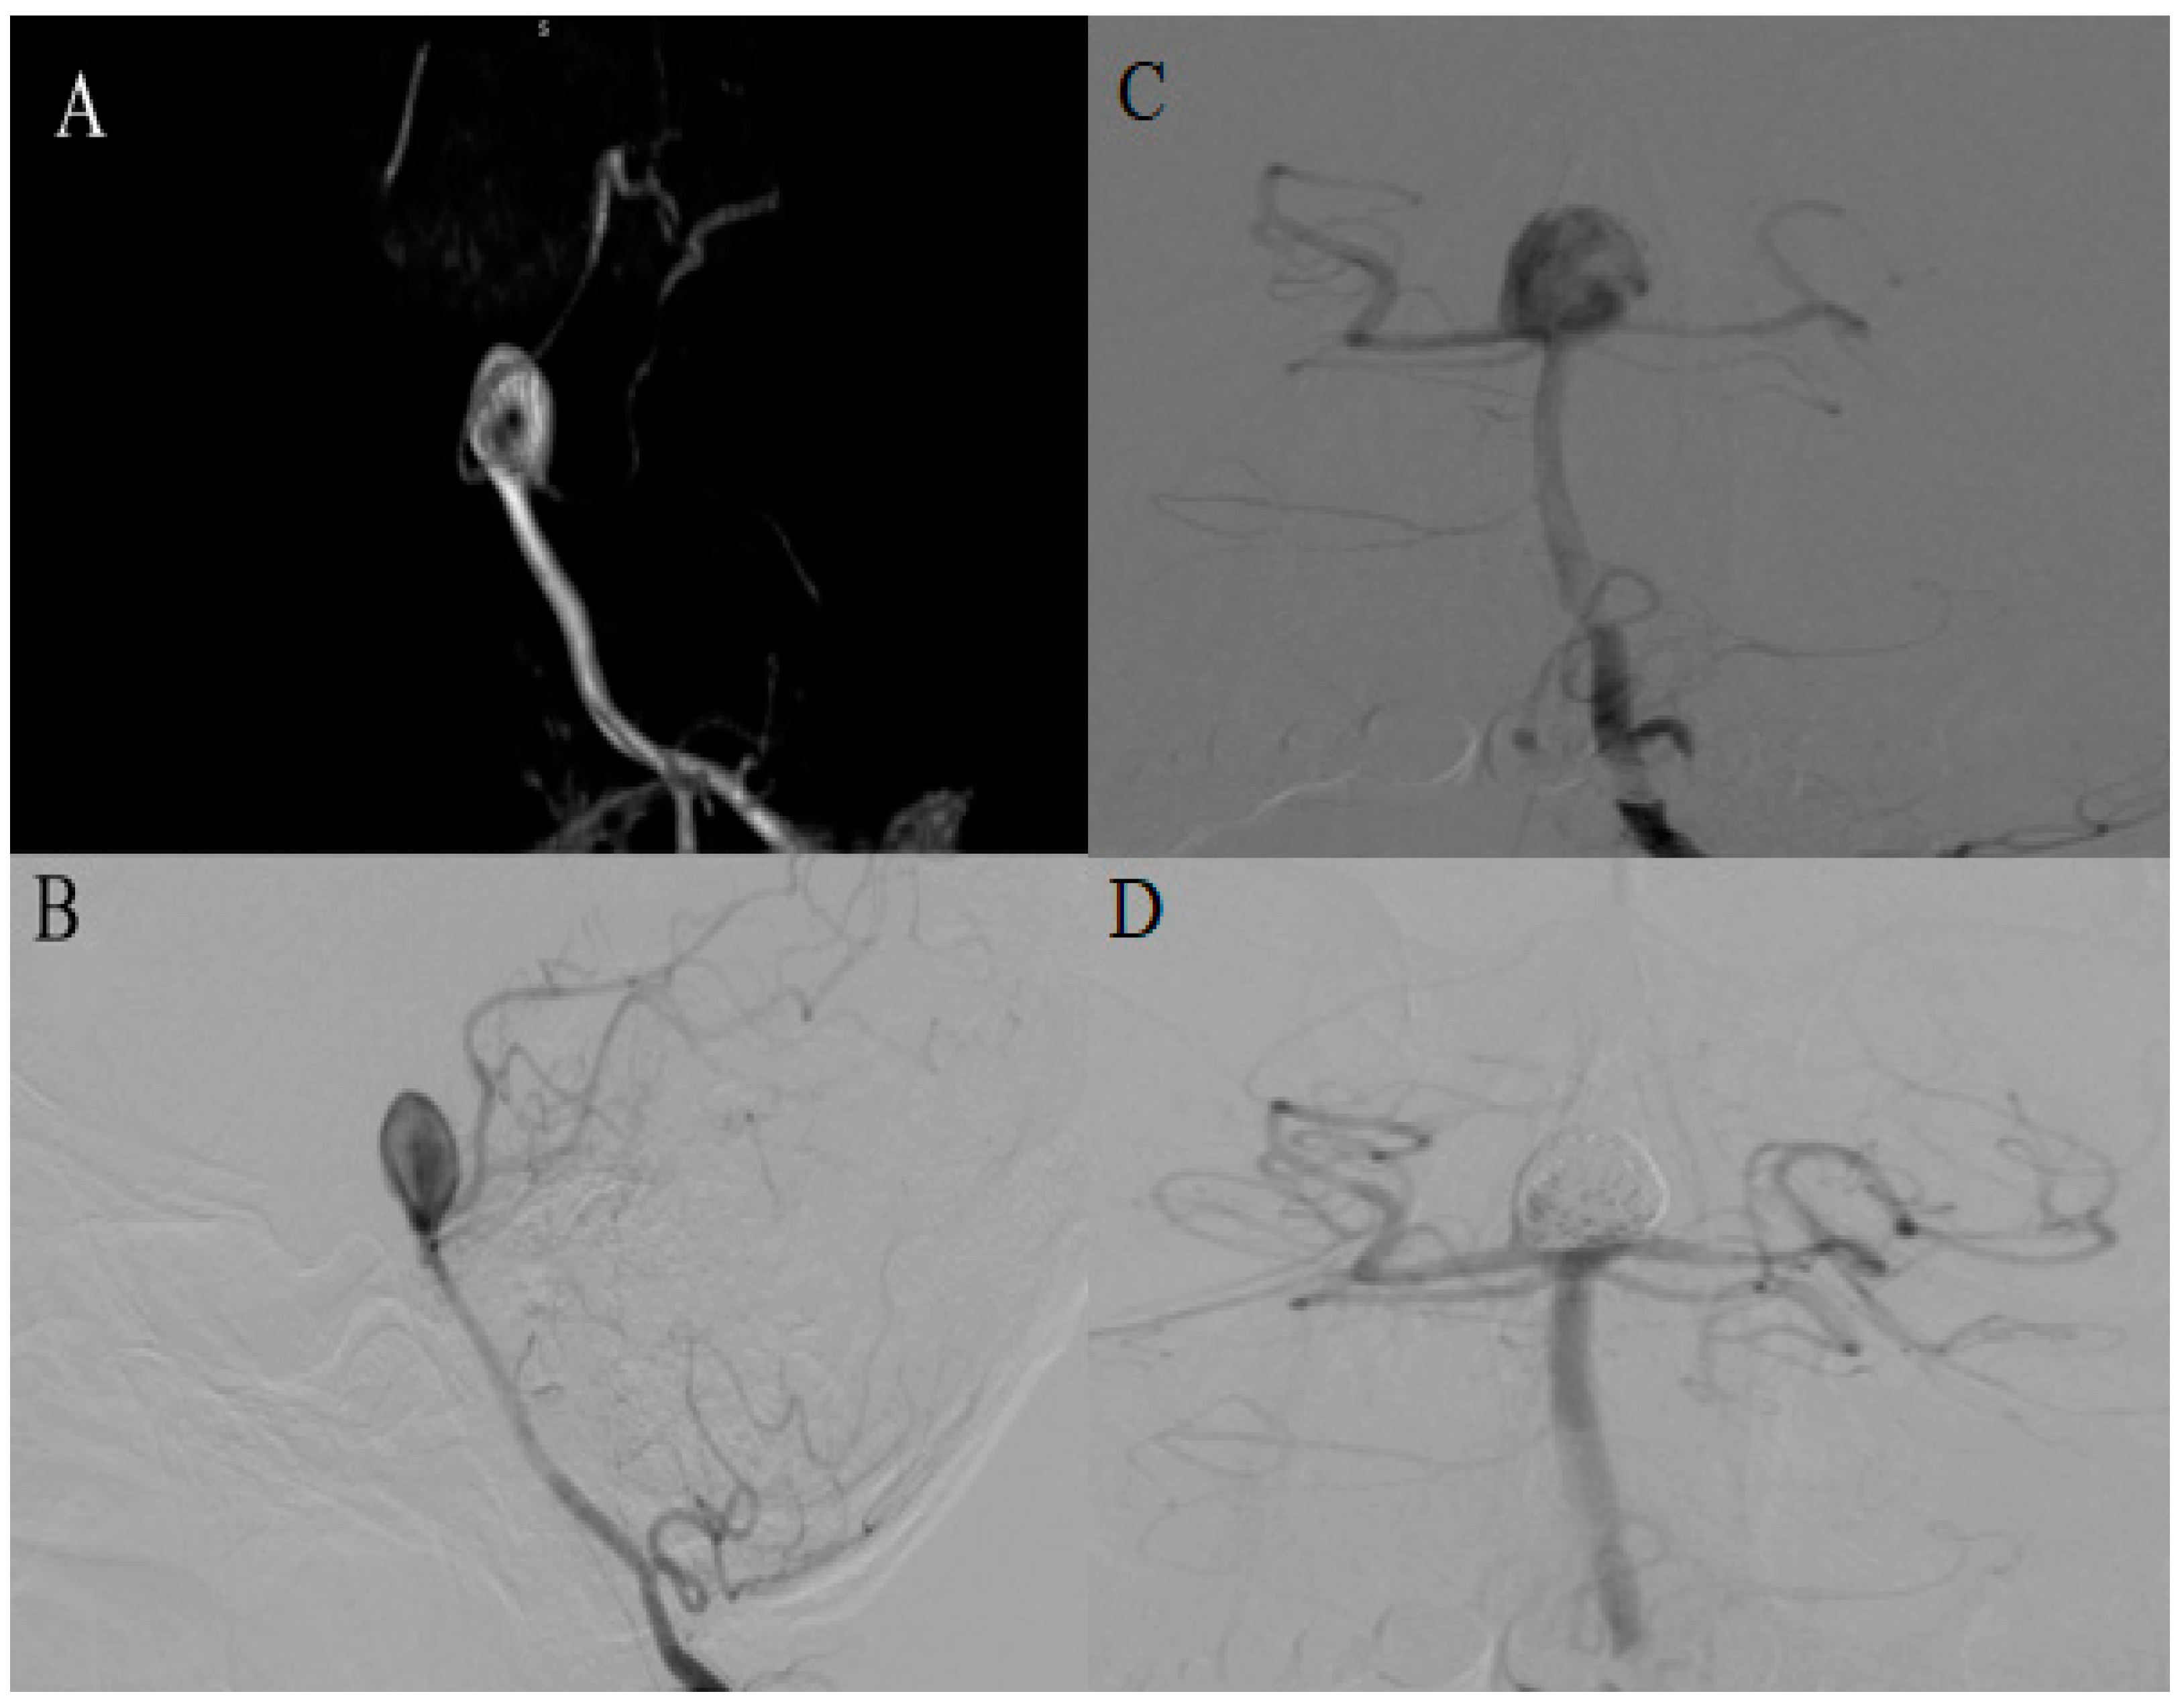

2.4. Case 4

| 4 | 48 | F | 25 mm | Giant | BA tip | N/A | Headache, vertigo | EVT (stent + coiling) | Yes (residual volume 19 mm × 9 mm) | Residual volume (7 mm × 5 mm) | Pending | Pending | N/A |